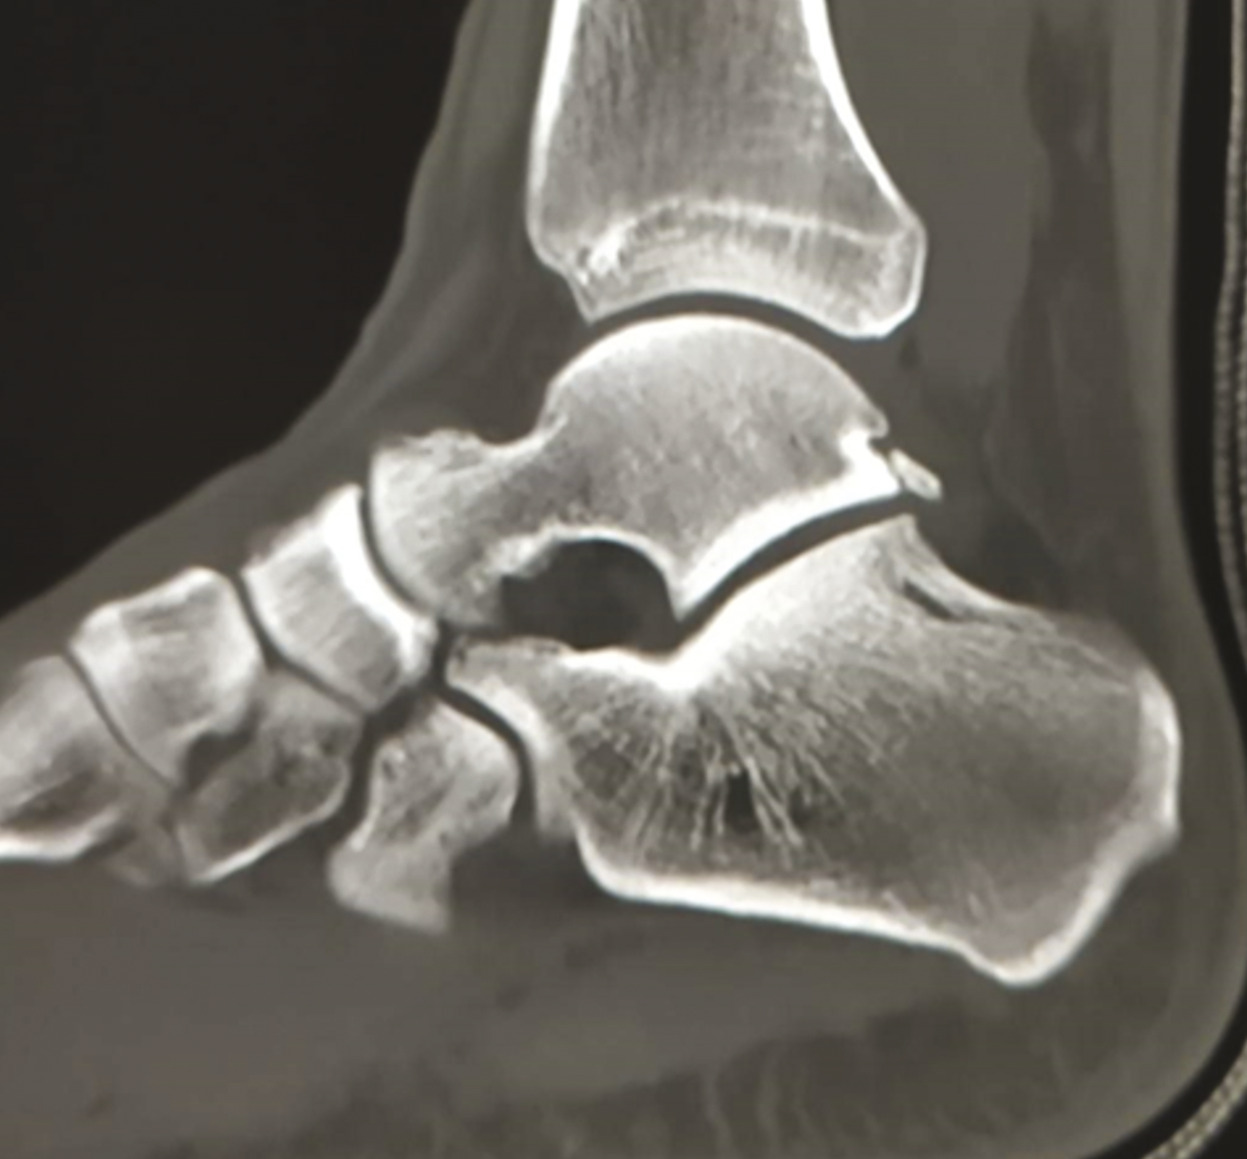

La radiographie laisse supposer la présence d’une fracture du calcanéum ou talienne (fig. 1 ) explorée au scanner. Le scanner retrouve une fracture ancienne de la face antéro-médiale du talus et une fracture récente du rostre du calcanéum (fig. 2 ).

L’atteinte des tubérosités postéro-médiale (fracture de Cedell)1,2 et postéro-latérale (fracture de Cloquet-Shepherd) du talus sont des équivalents d’entorse grave avec arrachement osseux.3 La fracture de Cedell est rarement vue à la radio, expliquant le retard diagnostique fréquent (chez ce patient, elle est passée inaperçue ; la corticalisation du fragment talien montre que la fracture est antérieure à cet épisode d’entorse) ; le diagnostic positif est souvent fait lors d’un scanner en cas de douleur traînante. Il faut néanmoins distinguer cette fracture de la présence d’un os surnuméraire (os trigone) pouvant être localisé au même endroit.Cliniquement, on peut l’évoquer devant une douleur et un œdème en postéro-inférieur de la malléole interne. La douleur peut être déclenchée à la dorsiflexion de l’hallux, car le tendon du fléchisseur de l’hallux passe dans le sillon formé par les deux tubercules postérieurs du talus. Le mécanisme en cause est une dorsiflexion-pronation induisant une fracture par avulsion ou une flexion plantaire-supination (par exemple en glissant d’une marche d’escalier) ; cette fracture est fréquente chez les footballeurs ou les danseurs.4,5 La prise en charge dépend du type de fracture : on a souvent recours à un traitement orthopédique ; en cas de persistance des douleurs, une ablation du fragment peut être proposée.3,4